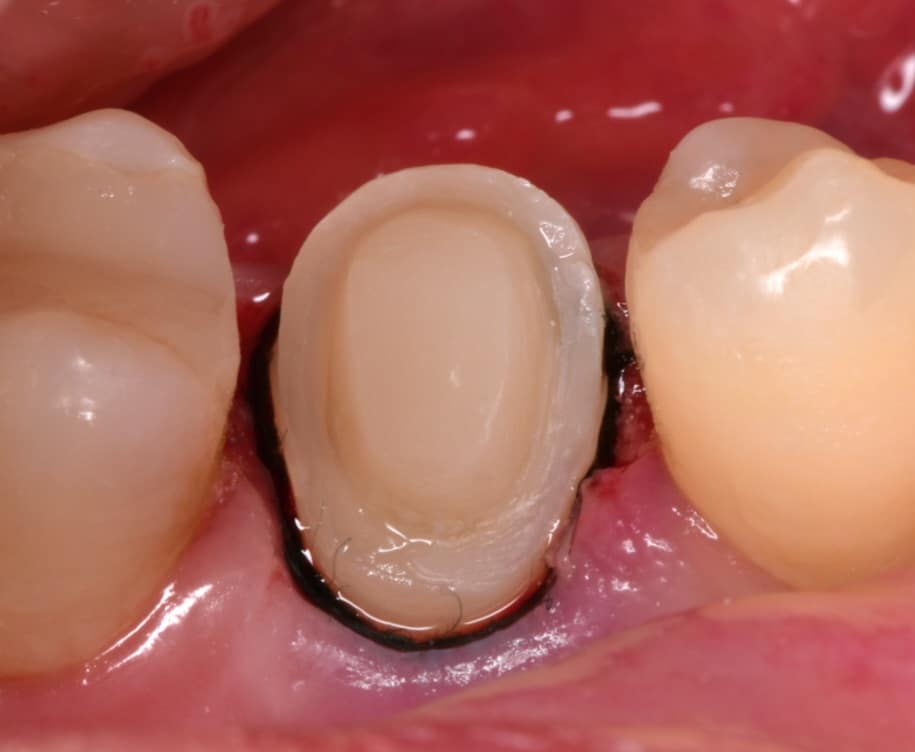

Isolation, look to the amount of tooth structure left under the gingival tissue, dentin quality looks good for bonding, so lets go with adhesive dentistry

Band adaptation, IDS with gold standard clearfil SE bond, RC with flowable composite,Ribbond placed inside the ever x flow, Ever x flow for dentin replacement,

Biobase ready